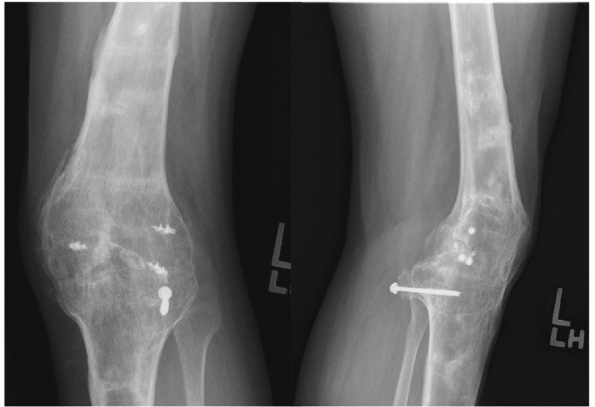

![]() |

|

FIGURE 54-1

Medial compartment arthritis evidenced by medial joint space narrowing in a 24-year-old man, 5 years after a complete knee dislocation with popliteal artery injury (KD IIIM). |

FIGURE 54-2

Anteroposterior and lateral radiograph of a knee arthrodesis performed as a salvage procedure for severe tricompartmental arthritis following a knee dislocation. |